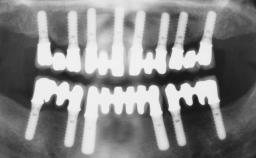

| Jaw | Maxilla and Mandible |

| # of Teeth | 9 |